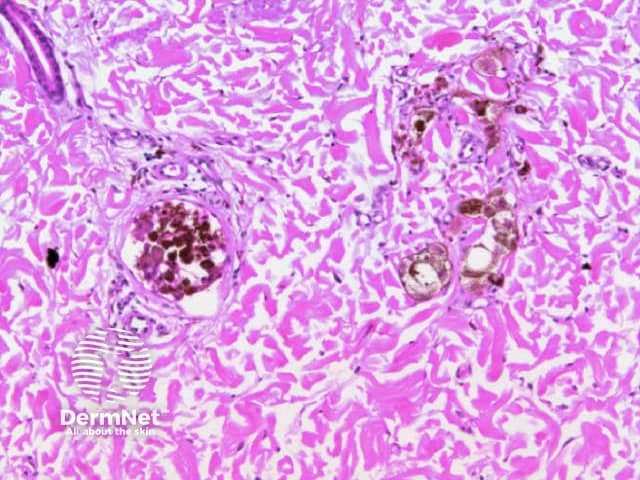

Dots are small enough to have no discernable shape at the magnification provided by a dermatoscope. They represent melanin, or occasionally haemosiderin, with the colour depending on the level of the pigment within the skin in the case of melanin. Dots may be black (superficial epidermal melanin), brown (basal epidermal melanin or superficial dermal haemosiderin), grey (papillary dermal melanin) or blue (reticular dermal melanin). They are usually present in association with another pattern. Brown or grey dots are occasionally found without another pattern (Figures 34-36). Red dots, representing a vascular pattern, are discussed later.

Black dots result either from pagetoid pigmented melanocytes or free pigment within the stratum corneum. Brown dots reflect either small nests of melanocytes in the basal epidermis, focal pigmented keratinocytic proliferation, as seen in some forearm solar lentigines, or superficial dermal haemosiderin deposition. Grey dots are due to melanin pigment within the papillary dermis, either free, in small nests of melanocytes or, more commonly, in melanophages. Blue dots reprresent deeper dermal melanin. The differential diagnosis of dots on dermatoscopy is shown in Figure 34.

Figure 34a Figure 34b Figure 35 Figure 36